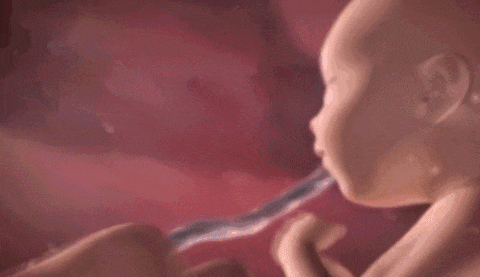

第3张图:揉眼睛

大约20周左右,宝宝的视力已初步发育,能隐约感受到光线。因此有的胎教会建议妈妈适当晒晒太阳,或用手电筒温和地照照肚皮。

透过羊水,宝宝能感受到微弱的光亮。有时候,他们还会自己揉揉眼睛,探索身体的小部位呢!